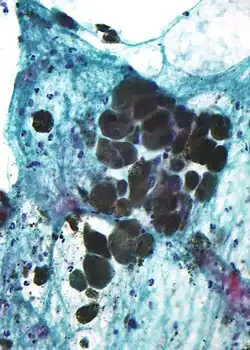

Microscopic appearance

Melanin is brown, non-refractile, and finely granular with individual granules having a diameter of less than 800 nanometers. This differentiates melanin from common blood breakdown pigments, which are larger, chunky, and refractile, and range in color from green to yellow or red-brown. In heavily pigmented lesions, dense aggregates of melanin can obscure histologic detail. A dilute solution of potassium permanganate is an effective melanin bleach.[55]